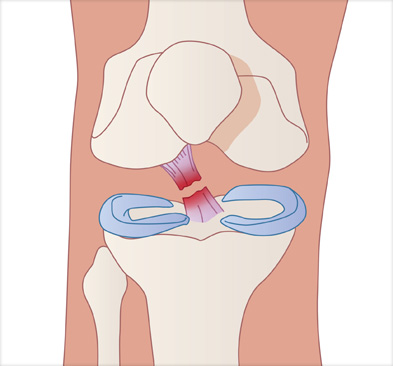

경골과 대퇴골 사이에 남아 있는 전방십자인대 제거

경골과 대퇴골 사이에